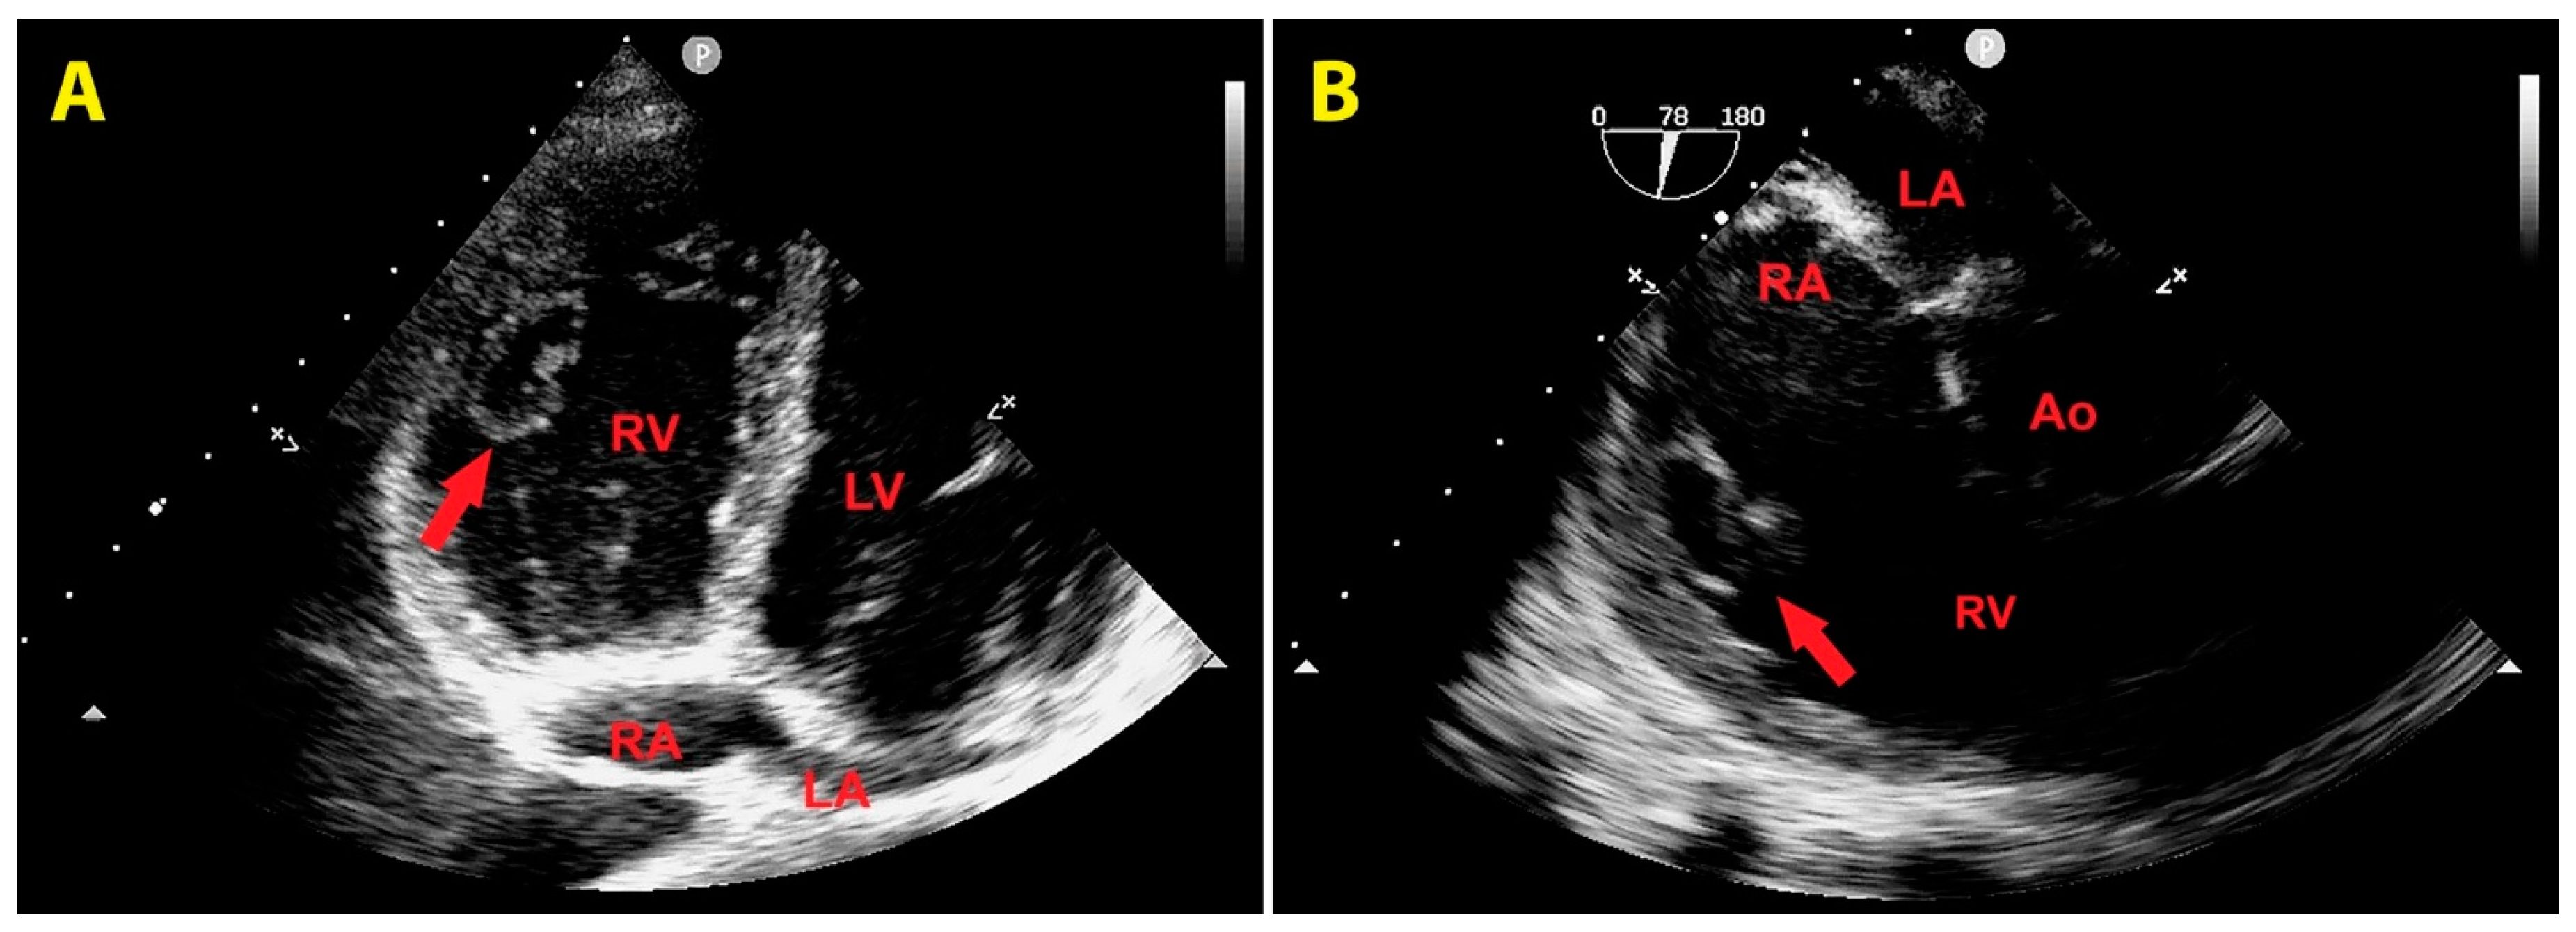

A repeated TTE during the stay in the ICU demonstrated a slight reduction in RV mass size (3 cm x 2 cm), that changed its echogenicity, being characterized by an anaechoic central space and a hyperechoic border (Figure 5A). The same echocardiographic findings of the RV mass were confirmed from a RV focused mid-esophageal section obtained during TEE (Figure 5B).

Figure 5. (A) Transthoracic echocardiography. Right ventricular focused apical four-chamber view, demonstrating a slight reduction in right ventricular mass size (red arrow), characterized by anaechoic central space and hyperechoic border. (B) Right ventricular focused mid-esophageal section, showing the same echocardiographic features of the right ventricular mass (red arrow) observed from the transthoracic approach. Ao, aorta; LA, left atrium; LV, left ventricle; RA, right atrium; RV, right ventricle.